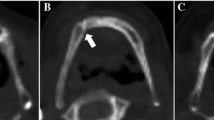

For each hyoid bone, every axial CT slice was visually inspected in the Region of Interest tool in Analyze. The slice with the smallest distance between the hyoid body and the greater cornua on each side was used for fusion ranking using the following four ranks as defined in Fig. 1: 0. Distant non-fusion, 1. Non-fusion, 2. Partial-fusion, 3. Fusion. Fusion ranks were assigned to each side of the hyoid bone separately. Figure 1 also shows the 3D model and CT scan of the hyoid bones with each ranking. Hyoid bone fusion rankings entailed assessment of the hyoid bone in multiple planes bilaterally on CT images instead of the 3D hyoid models as it was often difficult to rank the degree of fusion present unless the CT slices were examined (see Fig. 1).

Fusion rank definition with images showing the same fusion rank bilaterally. The 3D Hyoid bone models were created using image visualization and analysis software Analyze 11.0® (AnalyzeDirect®; Overland Park, KS). The axial slice from the CT scan with the smallest distance between the hyoid body and the greater cornua was used for fusion ranking but all axial, coronal, and sagittal views were inspected to accurately determine degree of fusion

After examining the fusion ranks on the right and left sides (see Laterality in “Results” section below), we established the following four fusion categories: I. Bilateral distant non-fusion, II. Bilateral non-fusion, III. Partial or unilateral fusion, and IV. Bilateral fusion. Note that categories I, II, and IV have the same fusion ranks on both sides whereas category III includes a combination of fusion ranks where fusion has begun on at least one side but has not been completed bilaterally. This includes partial-fusion (rank 2) on one side with either non-fusion (rank 1), partial fusion (rank 2), or fusion (rank 3) on the opposite side; or fusion (rank 3) on one side and non-fusion (rank 1) on the opposite side. Table 1 describes the four bilateral categories of hyoid bone fusion.